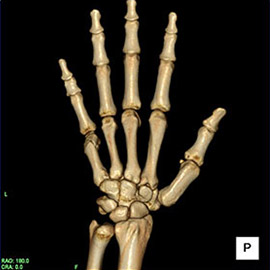

80列マルチスライスCT 検査 画像例

80列マルチスライスCTで撮影した画像

整形